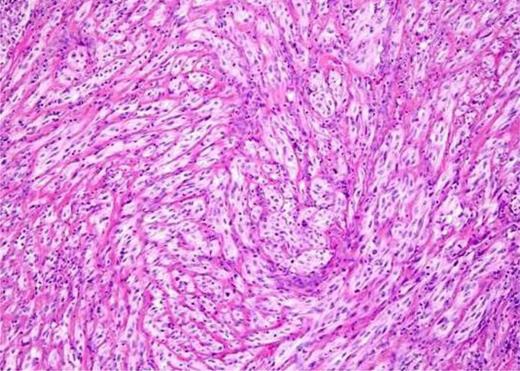

The patient underwent excision of the swelling from the right hemiscrotum under local anaesthesia. Resection was easily achieved. Histology of the sample showed circumscribed encapsulated partly spindled and partly mesenchymal cellular neoplasm arranged in sheets, trabeculae and whorled nests with a background of hyalinized stroma. The cells had uniform spindled to ovoid nuclei with a vesicular chromatin pattern and prominent central nucleoli with ill-defined cell borders and amorphophilic, eosinophilic and clear cell cytoplasms. The cells were also strongly positive for S100 protein and strong but patchy positive for Pan, cytokeratin AE1/3. The tumour also showed focal nuclear positivity for P63 and EMA but negative for smooth muscle actin, desmin and caldesmon (Figs 2 and 3).

Myoepithelial cells stained and enhanced, negative for smooth muscle actin, desmin and caldesmon.